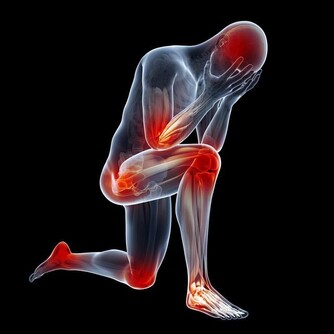

2、會減少人的壽命,尤其是男性的壽命同時和血管有關的中風機率會隨著增加。

3、會阻塞心臟動脈和使其變窄,更容易引發心髒病。

4、會使骨質疏鬆症的可能性變高,同時過多攝入膽固醇可導致牙周病、牙和牙隙之間的溝隙會擴大。